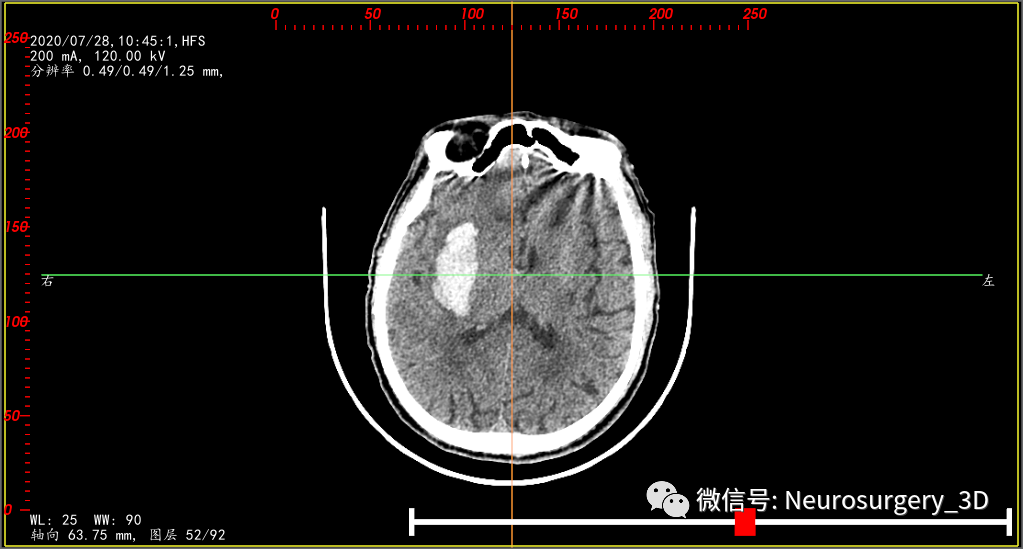

两天后的CT复查(2020年7月30日9:46)并测量不同区域的CT阈值,三维重建阈值选择45-100,包含低密度血肿区域。

是活动性出血吗?对比脑部活动性出血CT征象,一些文献报道:CT混杂征是由Li等在2015年提出的一种预测血肿扩大的影像标记,主要是指(1)血肿内存在边界分明的高低密度两种成分,(2)两种成分CT值至少相差18HU,且(3)低密度成分不包含于高密度成分中的一种征象。其形成的机制是血肿内凝固的血块在CT上呈现高密度,而低密度区域可能是由于破裂的血管仍在持续出血,血液尚未凝固所致。(下符CT混杂征片)

对比上述文献1、2、3还真像活动性出血,血肿较前两次CT检查又有增大现象,如果考虑活动性出血,手术方案无疑选择开瓣血肿清除了,年龄、身体耐术力、基础疾病等种种影响因素都是在活动性出血因素之后考虑的次要因素。

我中心近年来多次遇到这种CT征象:1、血肿内存在界限分明的高密度区域和低密度区域,且低密度区域呈半包围于高密度区域;2、多次CT复查,高密度血肿增加不明显,血肿扩大为低密度血肿;3、一般初次CT检查是高密度血肿,2-3天后血肿体积扩大,扩大的血肿为低密度血肿,高密度血肿无扩大。其形成机制考虑为长期饮酒或口服抗凝药物后,脑部小血管破裂出血致血肿凝固析出渗液,低密度血肿所含血清成分较多,为不凝液状态。这种形态血肿微创穿刺治疗血管比较理想,手术也证实,在微创手术中液态部分能较容易引出,起到迅速减压,缓解颅内压力的目的。

为了验证是不是活动性出血,再次复查颅脑CT(2020年7月30日15:10)如下:两次CT(间隔约6小时)对比,血肿形态无明显变化,证实并非活动性出血。